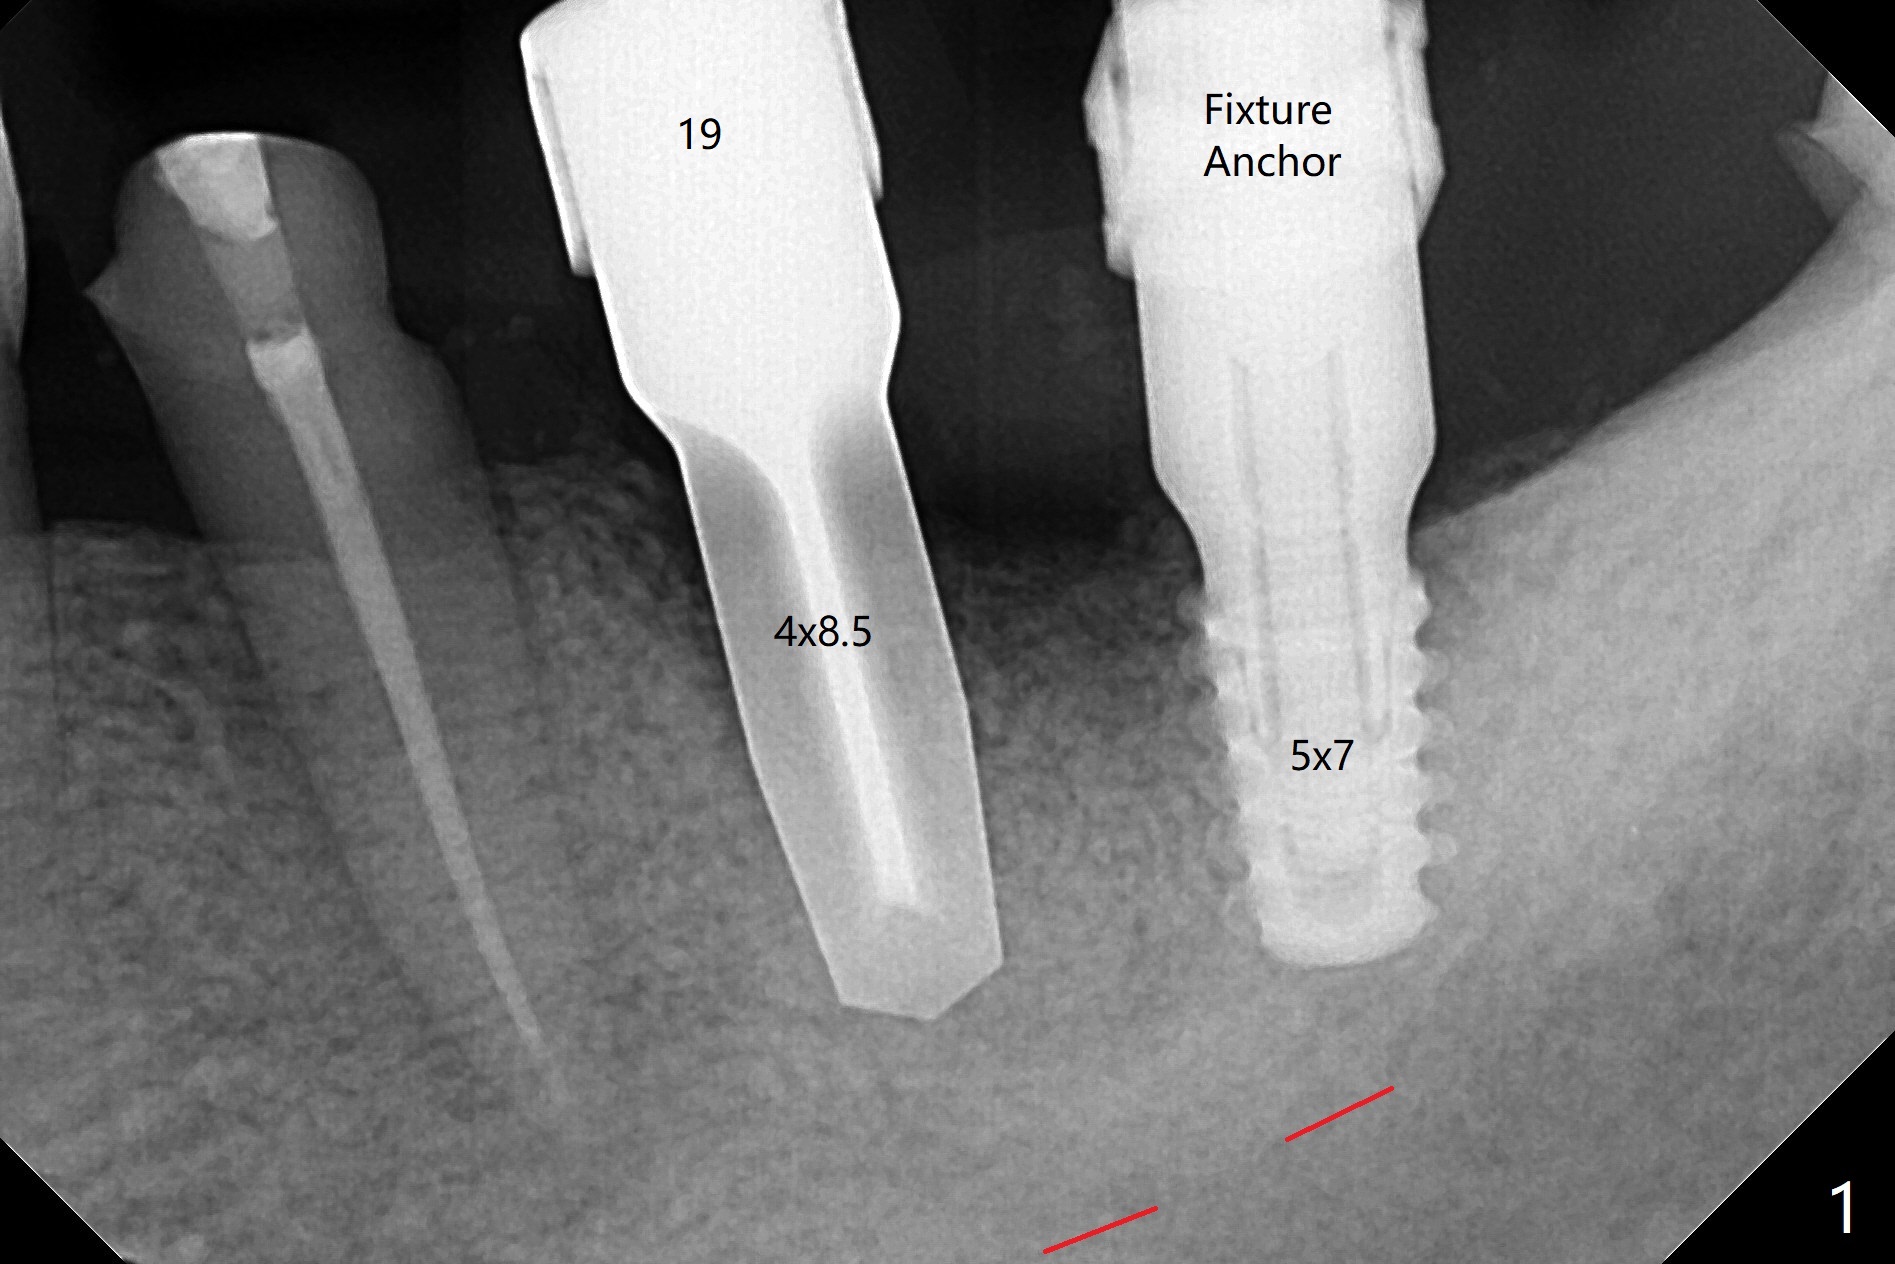

18,19导板远中架在17号牙残根表明树脂(图二:S),起到防止下沉作用,18号牙植体(~35Ncm)使用植体固定钉(fixture anchor mount no stop)植入,后者并且起着固定导板作用,增加19号牙植体植入稳定性,术中根尖片(图一)显示19号牙钻洞还不够深,之后钻头增加长度1.5毫米,4.5x8.5毫米植体扭力15-20Ncm(图二),但是与下齿槽神经管(红色虚线)还有很大距离,可能导板没有完全就位,植入后应该马上再次拍摄根尖片证实植入深度。由于18号牙区角化龈特别狭窄,切开种植,另外一个好处是容易植骨,但是术后疼痛明显,与上前牙即刻植牙(无切开)相比。今后尽量多做即刻种植。不过术后3个月包埋的植体表面有骨质覆盖(图三:*),二期手术很难找到愈合帽,而早些种植的上前牙植体由于过早受力,愈合不佳。当修复基台平面朝向颊侧,基台没有完全就位(图四:>)。当平面面对远中(图五:D),基台好像就位。